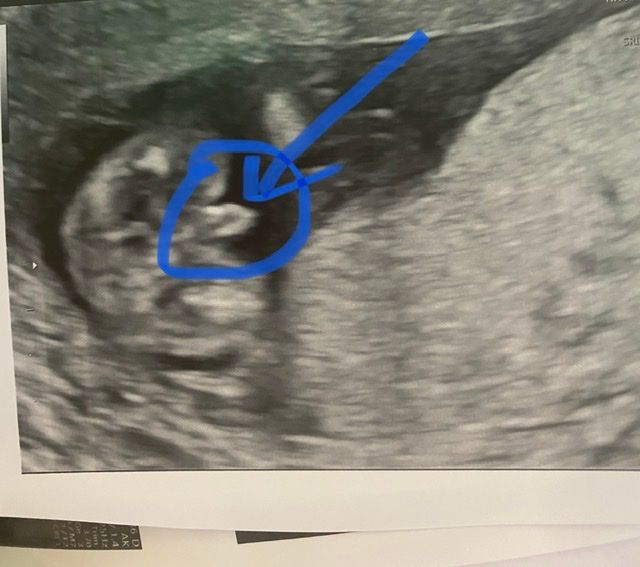

Добрый день. Была на Узи в 14 недель, врач сказала, что мальчик и показала фото. Мы с мужем немного в шоке от такого большого достоинства. Это точно половой член и почему он такого размера?

Ой, простите, мне так всегда смешно от таких вопросов, я то уже привыкшая 😁. Ну там сейчас стручок и совсем крохотные яички, а по мере роста яички будут расти, а стручок до нормального новорождённого размера уменьшится. Поздравляю с мужчиной 💐

Это половой бугорок пока что, а не член. Дальше он станет мужским или женским органом.

Вы немного неправильно поняли наверное)

Это же фотка снизу, а не в профиль)

Нормальный размер😁